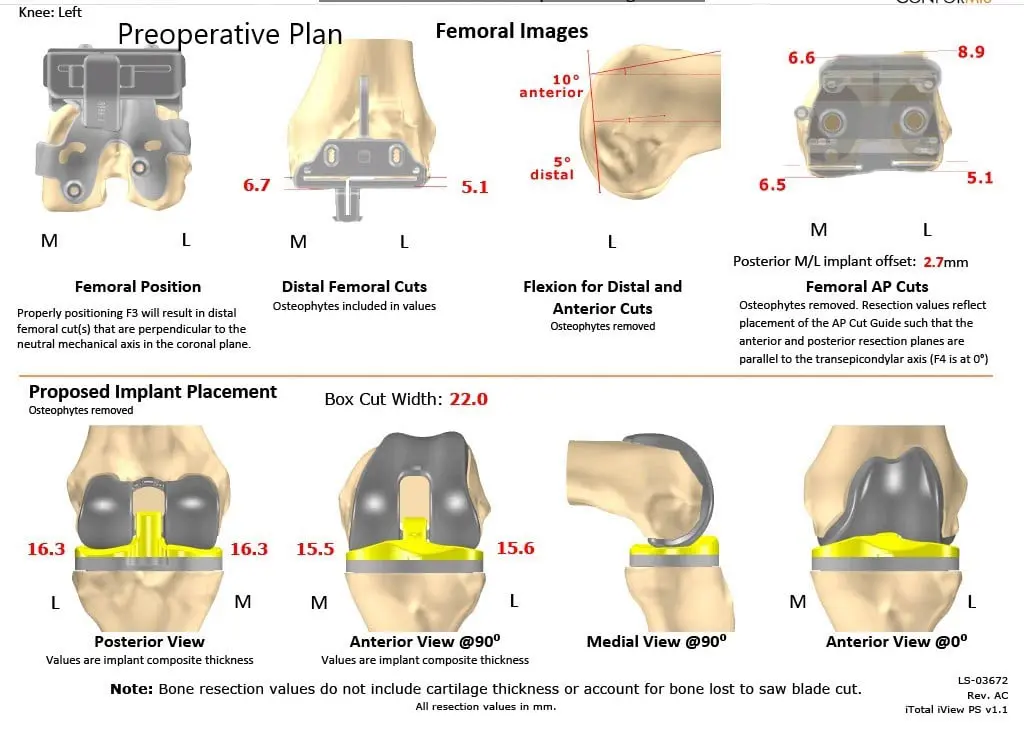

Several weeks before the surgery, a CT scan of the left knee was obtained. A unique 3D reconstruction was obtained from the data. This data was utilized to create unique patient specific implant. Additionally, disposable custom instruments unique for the patient’s knee were constructed. Custom implants and instruments ensured the best outcome of the procedure. A preoperative plan was made specific for the patient’s knee to preplan the bone cuts and offsets.

Complete Orthopedics patient-specific surgical plan for a custom left knee replacement in a 40-year-old male (scan 2)

Preoperative surgical plan outlining bone cuts and offsets